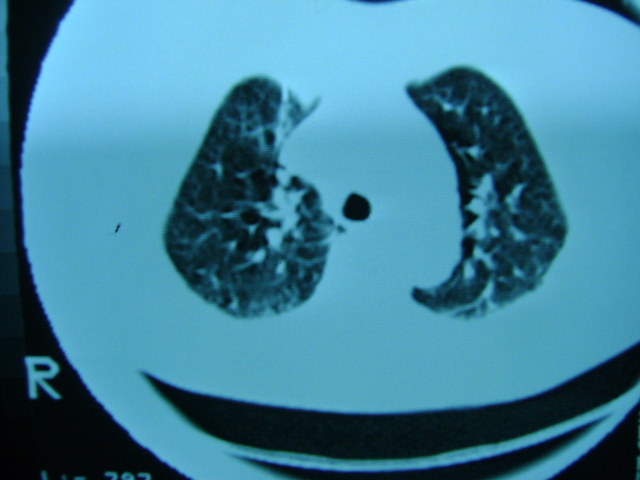

肺内应该存在感染

慢支 !不放心可追踪复查。

左肺门未见异常‘右肺有少许感染,图象质量不好

扫描所示未见明显异常!建议结合临床